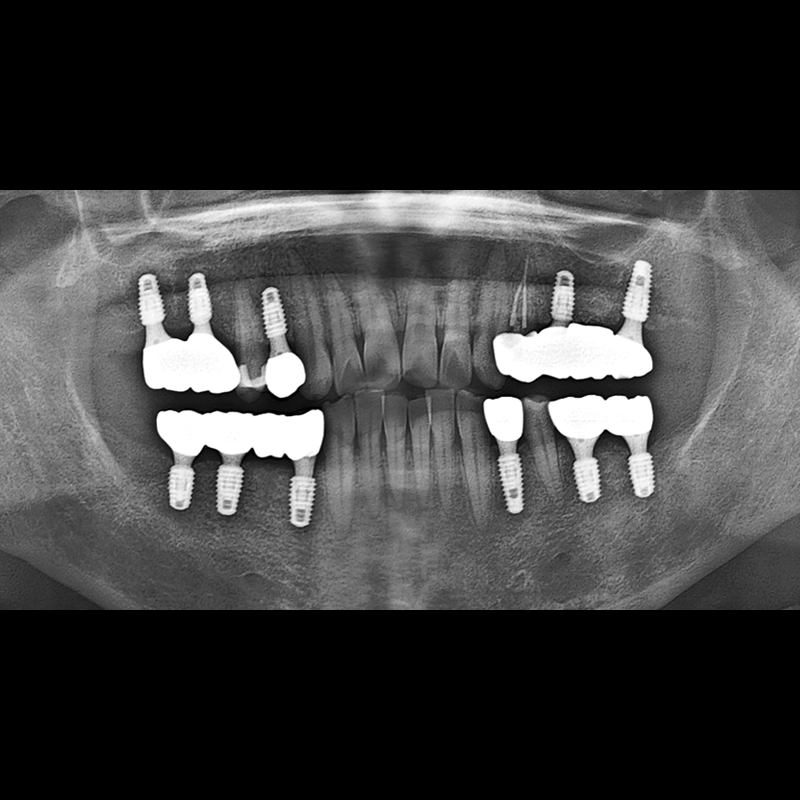

BEFORE AFTER

임플란트 전후사진 2025.12.10

결손된 치아 부분과 살리기 힘든 치아 위치에 임플란트를 식립하였습니다.